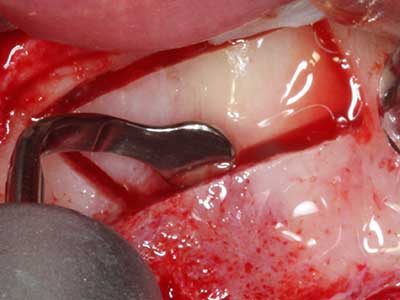

Пиезохирургията има допълнителни предимства при събиране на костни блокове. В допълнение към високата прецизност при остеотомията, описана по-горе, употребата на фините режещи накрайници значително намаляват загубата на материал. Голяма загуба на материал по време на събиране може да се очаква с дебелите накрайници, особено при употреба на борери Линдеман (Lakshmiganthan, Gokulanathan et al. 2012). Базалното разделяне, което е необходимо, особено за присадка на блок при ретромолар, е улеснено от специално създадени правоъгълни триони. В резултат на това, пиезохирургията е разглеждана като прецизна, улеснена и безопасна процедура за събиране на костни блокове в ретромоларното пространство (Happe 2007) (Фиг. 1-12).